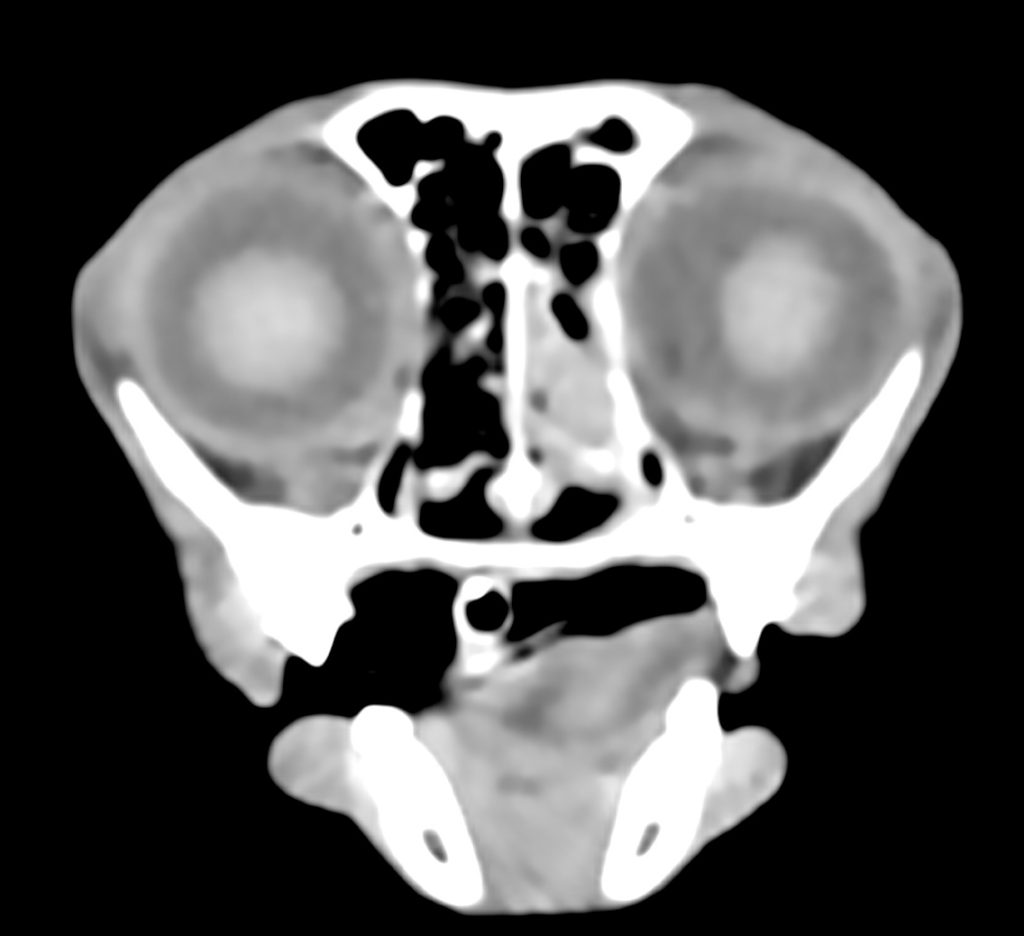

単純CT検査では、鼻腔内に貯留物が認められました。

造影CT検査では、鼻粘膜の造影増強は認められましたが、貯留物は造影増強が認められず、

炎症による鼻汁の貯留が疑われました。また、異物や腫瘍を疑う所見は認められず、

鼻腔の周りの副鼻腔という空間にも、炎症などの異常は認められませんでした。

以上の所見から、慢性鼻炎と診断しました。